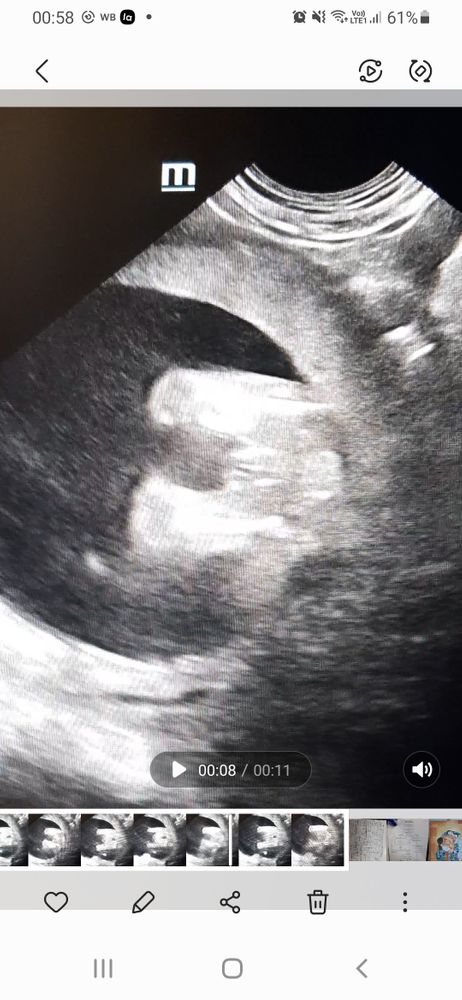

Девочка же? Узи 16 неделя, вид снизу

Больше на мальчишку похоже

На втором фото прям половая щель видна))) как по мне то девочка) Изображение Вот так наш пацан выглядел на УЗИ)

Может ракурс конечно такой, но вообще у нас по другому «три полоски» выглядели, не выпирали так Но вроде на девочку похоже да)

Девочка на нижнем фото видно , просто губки опухли

Писюна нет, пирожок есть но как то странно. У моей было немного по другому

А врачь вам разве не сказал? На нижнем девочка, а верхнее не очень удачный ракурс, писюн может и вверх смотреть и на бок

Соня , врач на узи сказала, что не понятно, т.к. ребёнок ножки поднимал и пуповина мешала. Эти снимки я сама себе делала, я ветеринарный узист😄

Мальчик) мне сейчас делали УЗИ и вообще гладенько все было и сказали, что девочка, а тут все видно)

Леся, по мне так отчётливо 2 яйца)